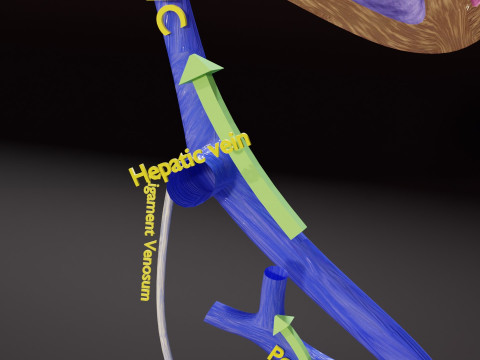

The model meshes include adult circulation versus circulation in Tetralogy of Fallot (TAF), arrow labels and text labels. The blood flow in a patient with Tetralogy of Fallot is outlined in this model. To contrast it to normal blood circulation a separate model of normal circulation is included. The Tetralogy of Fallot (OVER RIDING OF AORTA, PUL STENOSIS, VENTRICULAR SEPTAL DEFECT, RIGHT VENTRICULAR HYPERTROPHY), fossa, ligament teres , venosus, and arteriosus are duly depicted with proper labelling and blood flow directional arrows. Excellent model for teaching, demonstration and knowlegde of human body. The models include both procedural and image textures blend files separately. The texture file include diffuse, roughness and normal png and jpeg based on non overlapping UV maps.